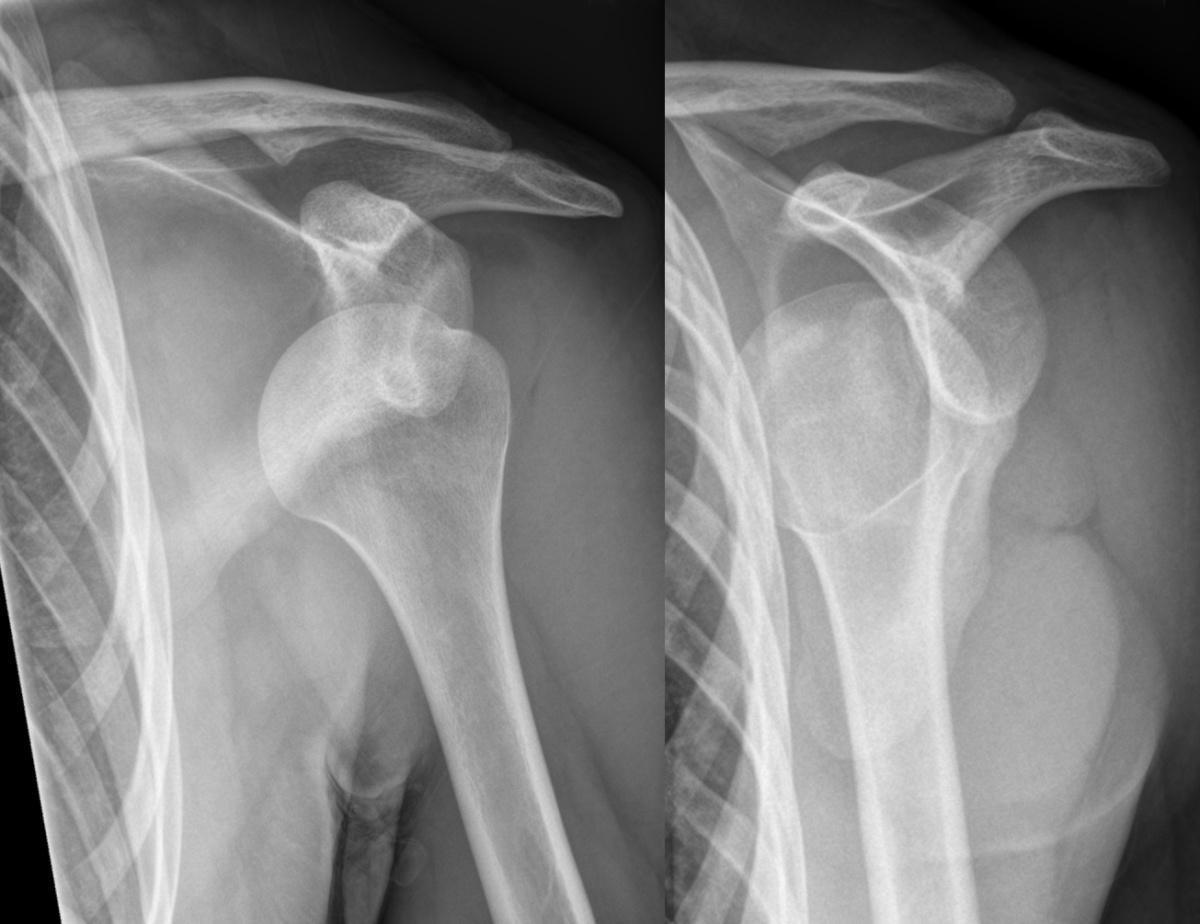

Hellerhoff - Own work, CC BY-SA 3.0, Link

Majorité des cas : luxation antérieure.

Radio de l’épaule (F + profil de Lamy)

Aspect radiologique PIEGEUX:

- disparition de l’interligne articulaire (trop bel aspect sphérique de la tête humérale)

- cliniquement : rotation externe impossible (signe de l’aumône)